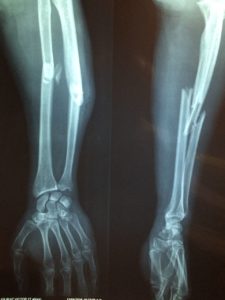

arbetsskada

image